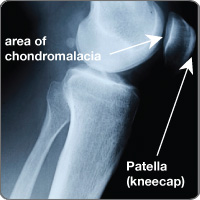

Chondromalacia patella

cond-chondChondromalacia patella is the softening of the cartilage on the underneath surface of the patella (kneecap). When this cartilage lining becomes softened it begins to breakdown producing irregularities to the underneath surface of the patella. Chondromalacia patella is caused by excessive and uneven pressure on the cartilage from structural alignment of legs and muscle imbalances that can be caused from rapid growth or poor technique of training skills. Pain is around the patella and can sometimes be behind the knee.